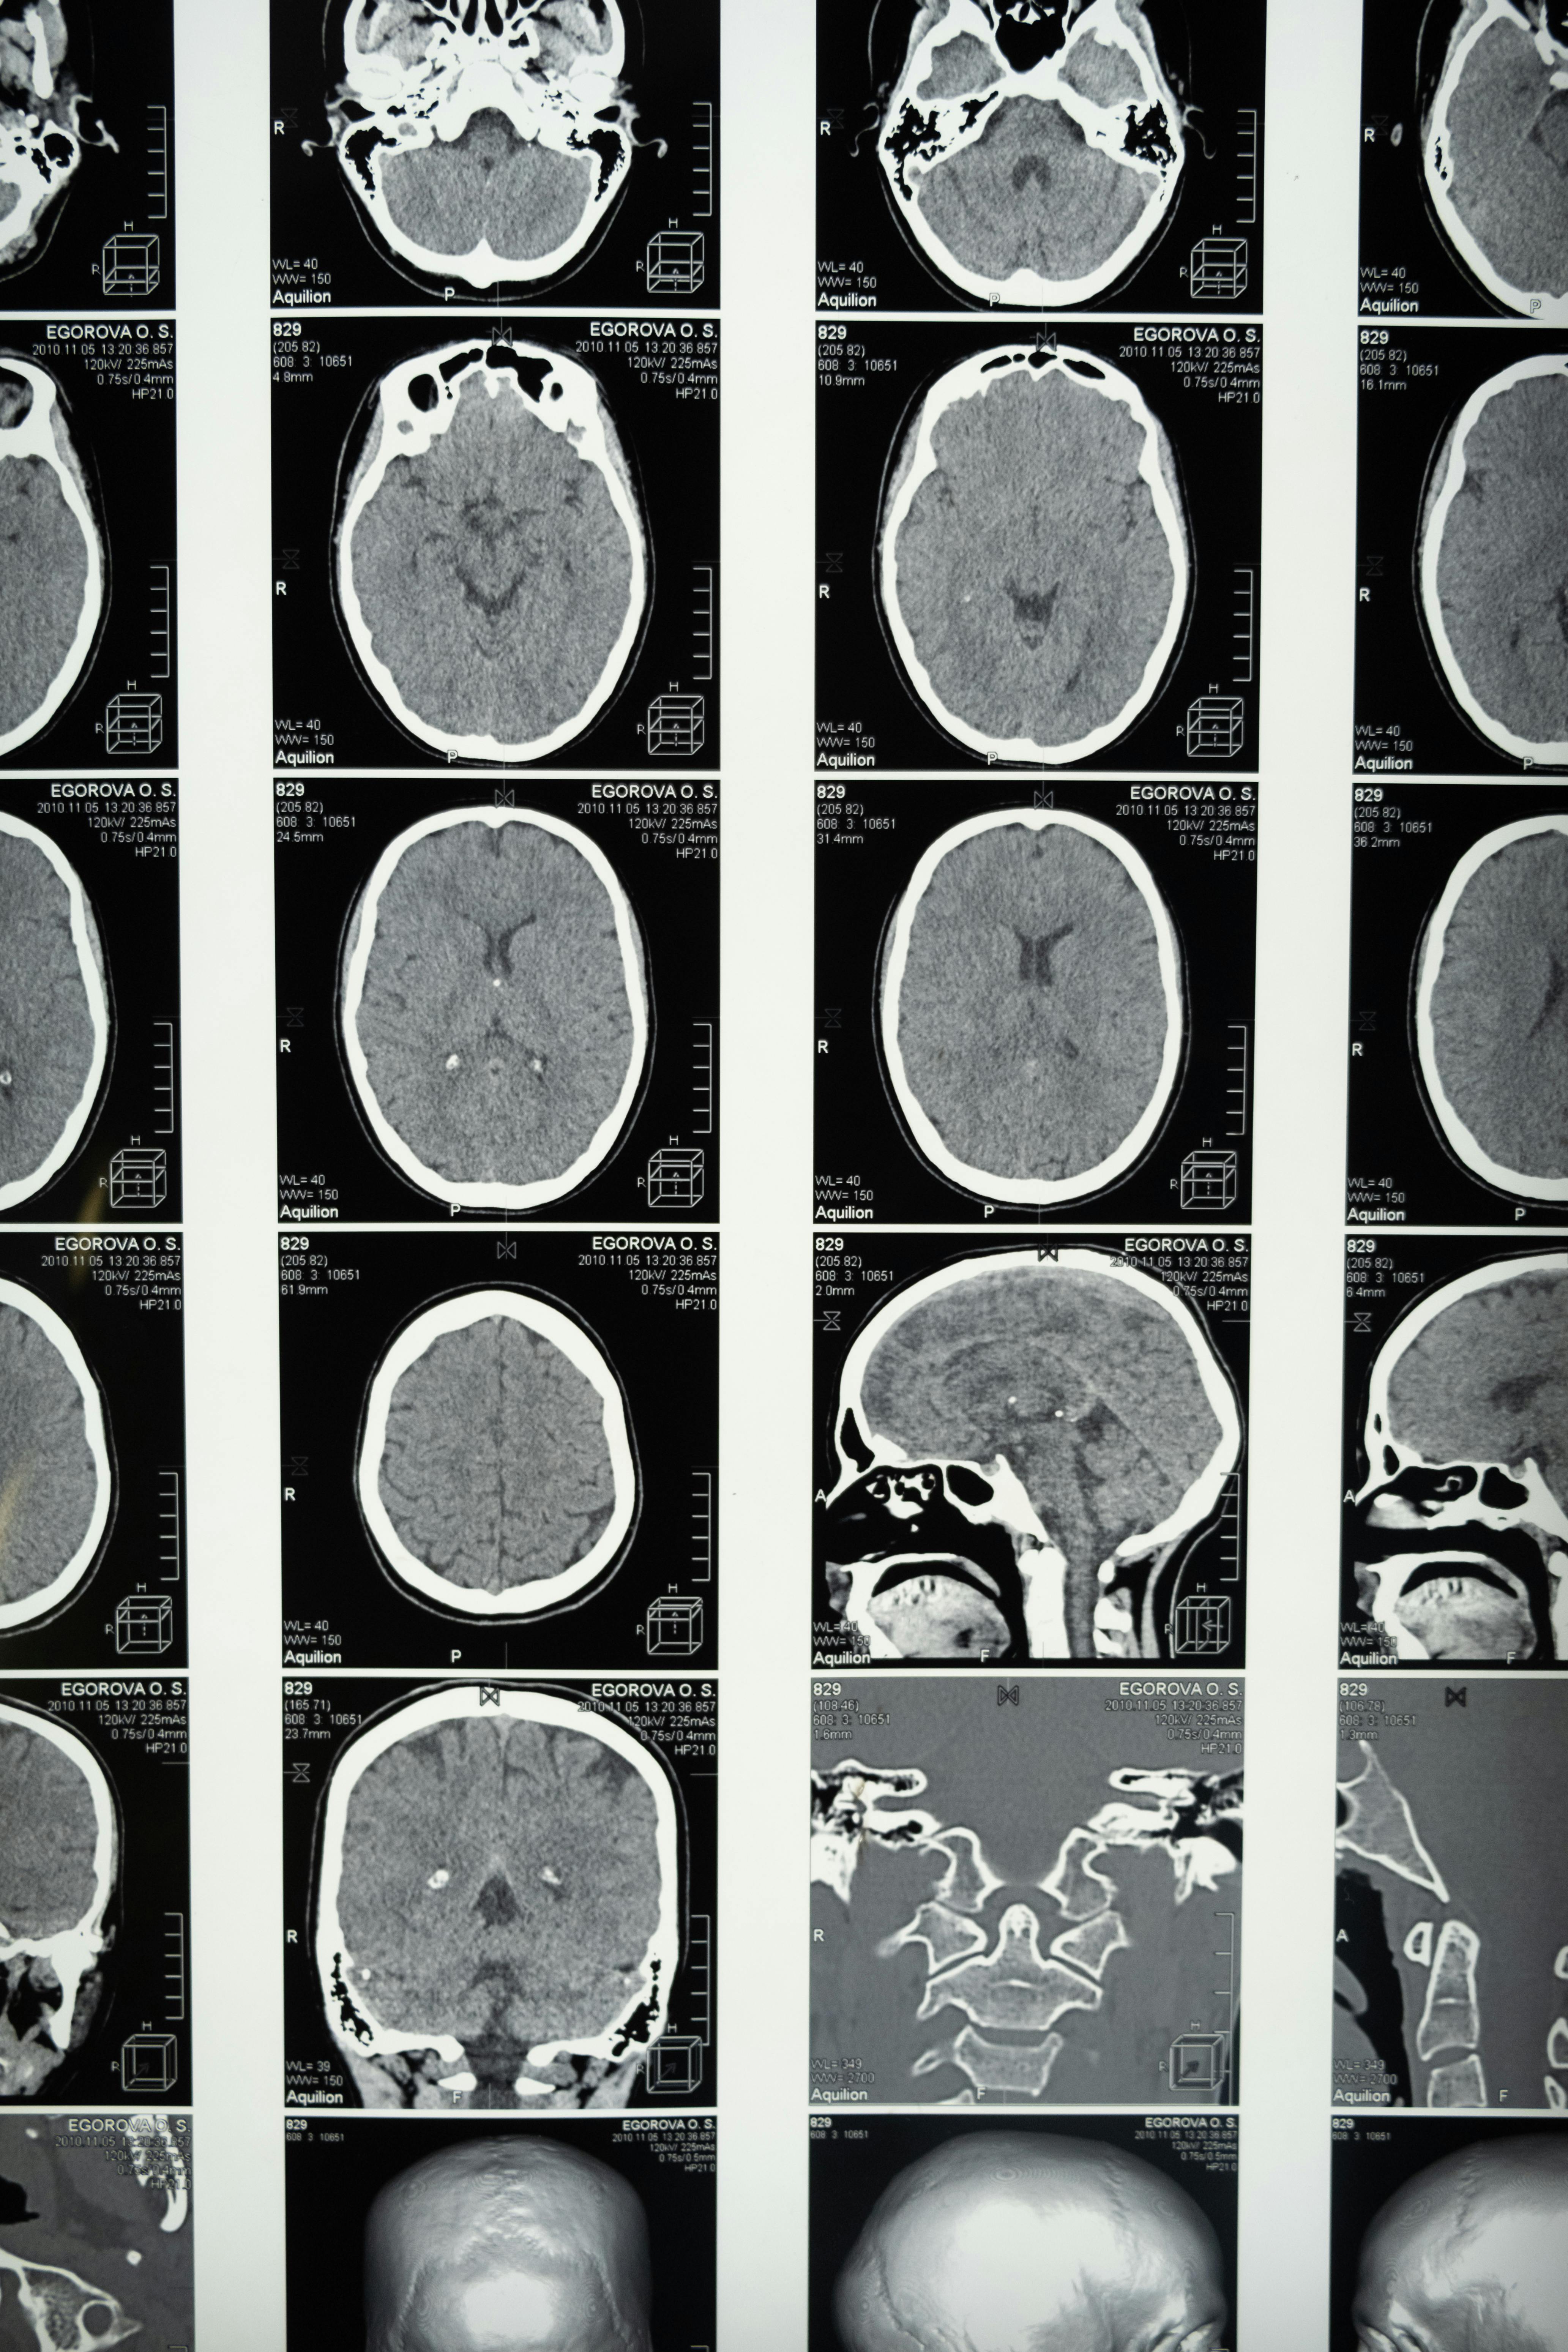

Our Neurology Department provides comprehensive evaluation, diagnosis, and treatment for disorders affecting the brain, spinal cord, and nervous system. Using advanced diagnostic tools — including MRI, CT, EEG, EMG, and nerve conduction studies — our board-certified neurologists combine clinical expertise with clear, timely communication. We focus on patient comfort, thorough assessment, and evidence-based therapies to improve function and quality of life.

We manage both acute neurological emergencies and chronic conditions, from stroke and seizures to migraines, movement disorders, and neuropathies. Our neurologists work closely with neurosurgery, rehabilitation, and primary care teams to ensure coordinated care. Each patient’s plan is individualized, combining medication, lifestyle strategies, and, when necessary, advanced interventions. We prioritize early diagnosis, proactive management, and continuous follow-up to help prevent complications and preserve neurological function.

Neurological health affects movement, memory, speech, sensation, and overall mental well-being. Conditions such as stroke, epilepsy, migraines, and neuropathies can impact daily life, but early detection and specialized care improve recovery chances and long-term outcomes. Our neurology team uses advanced diagnostics and personalized treatment plans to help patients maintain or regain independence.

You may need imaging (MRI/CT), EEG, EMG, or lab work depending on your symptoms.